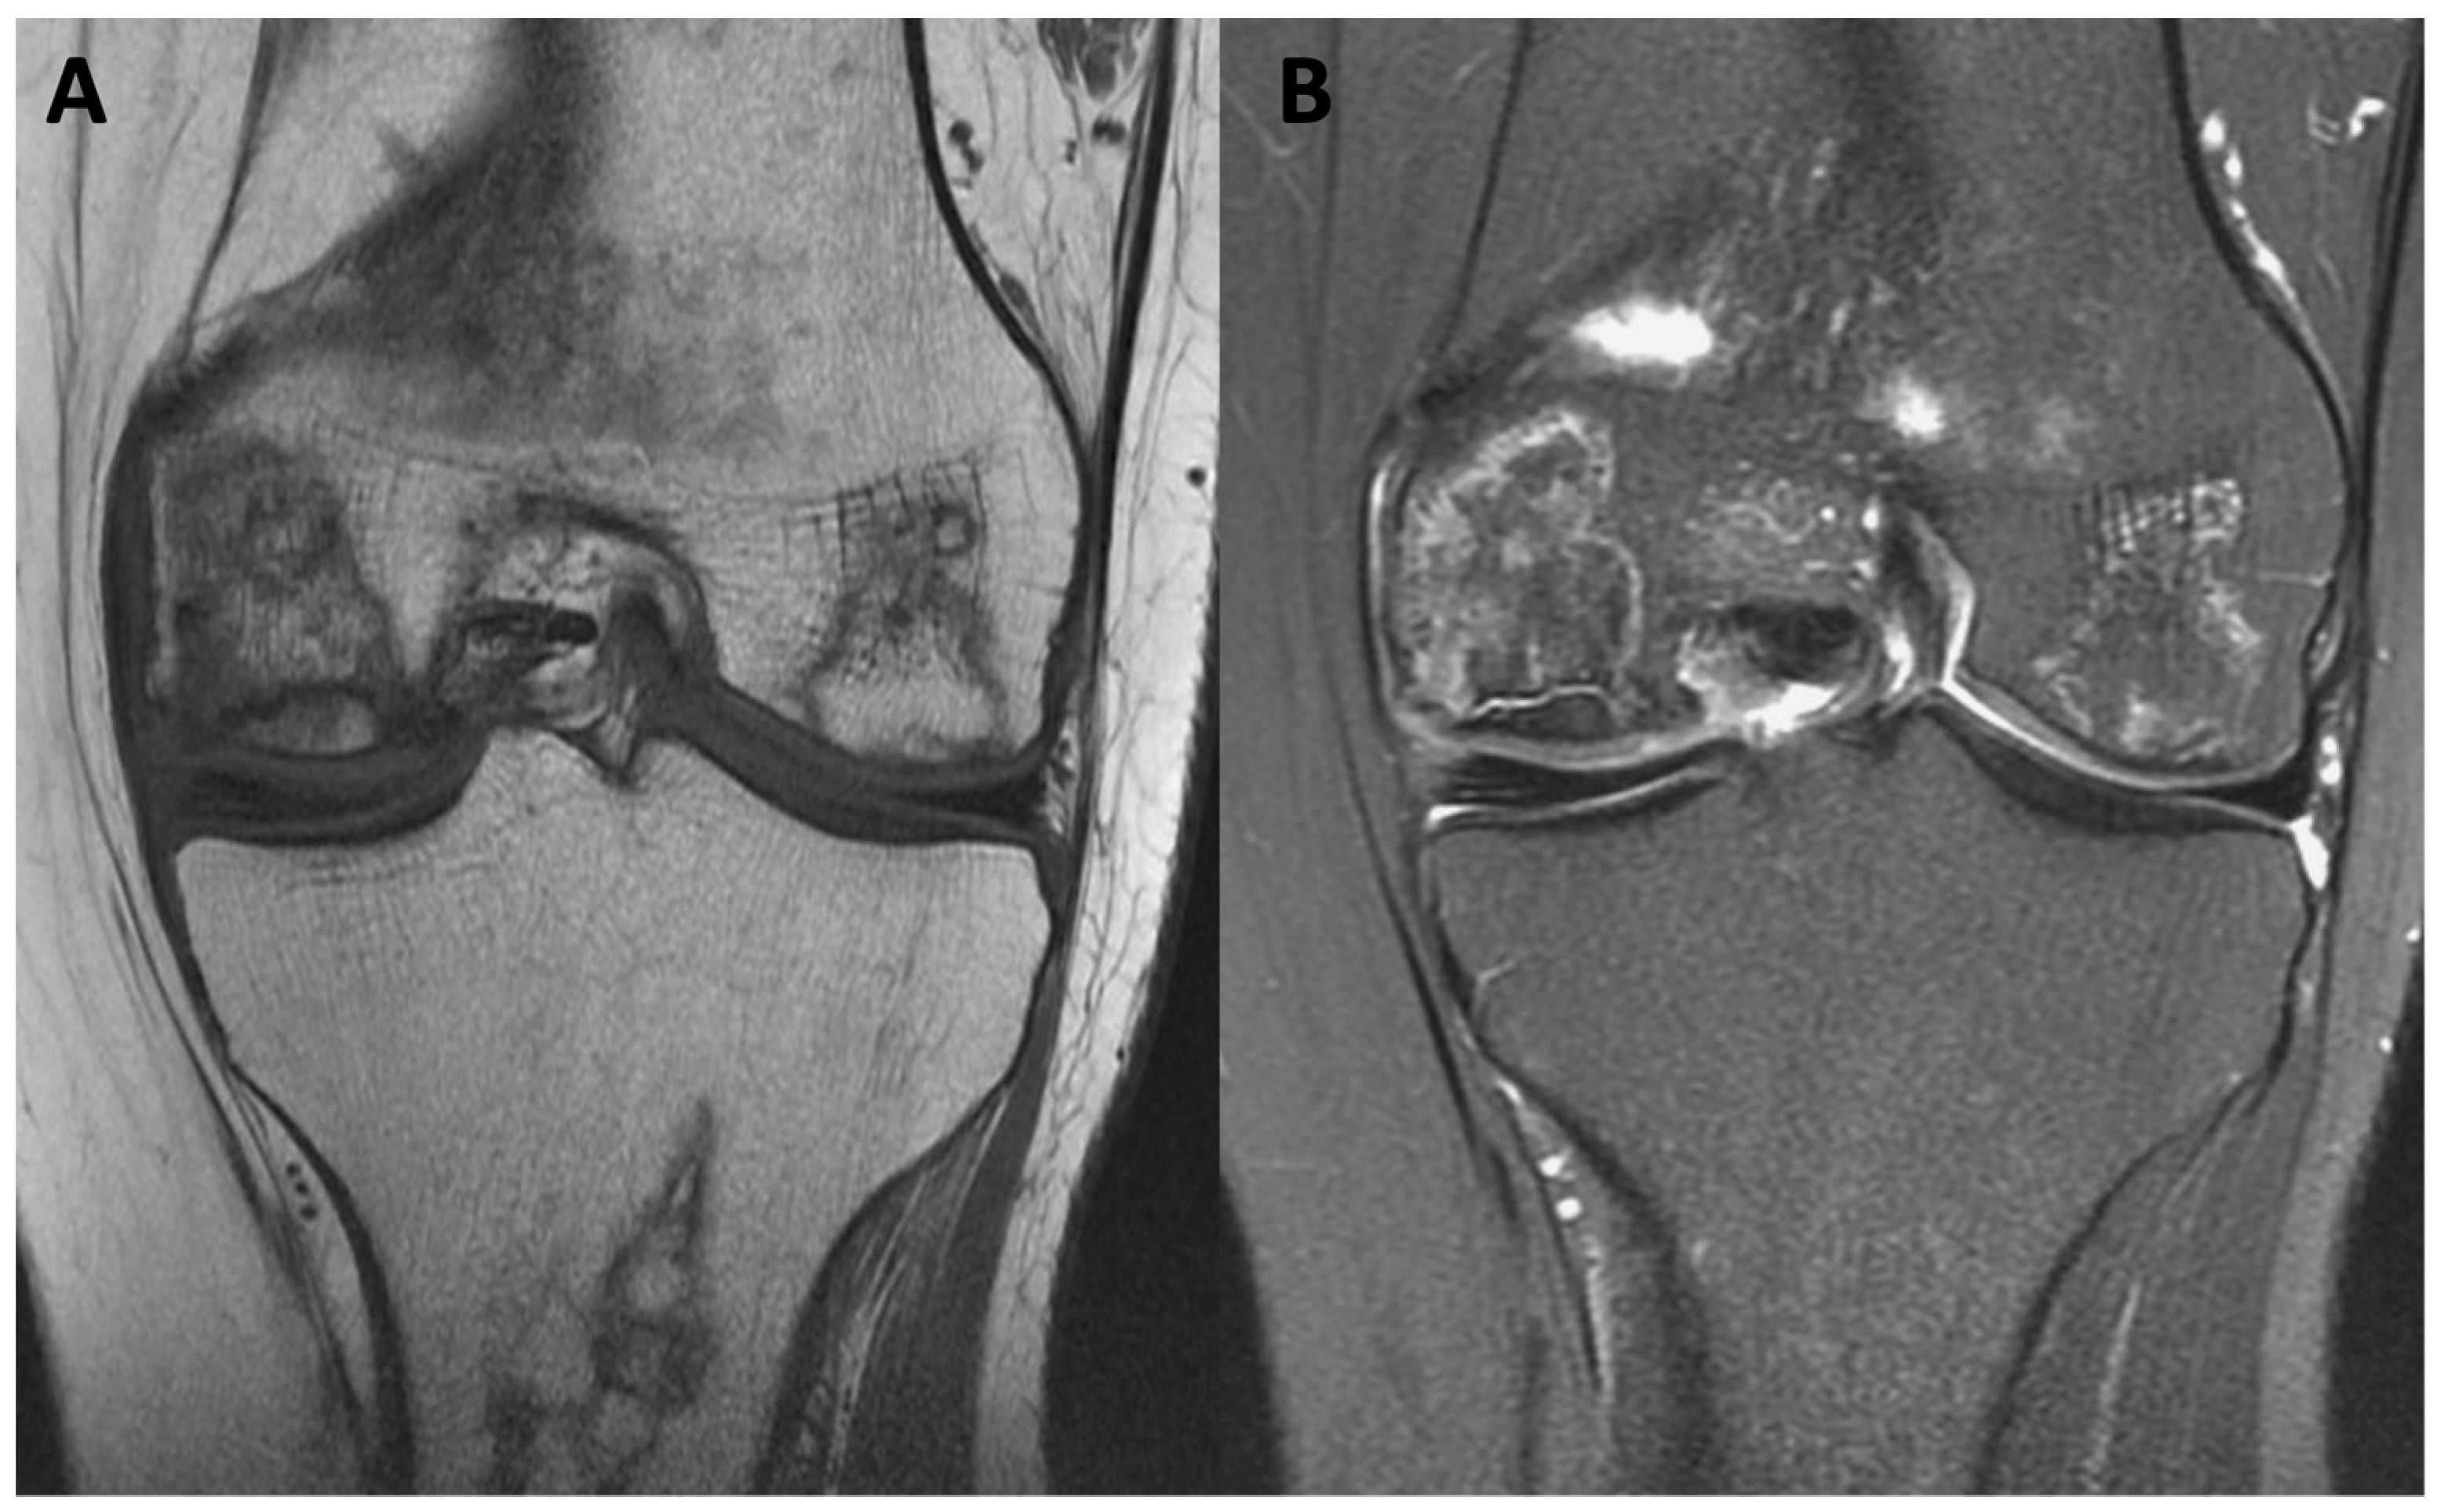

| MRI features | T1-weighted images display a single-density, low-signal intensity line. T2-weighted images display a high-intensity line with early necrotic-viable bone interface. | In T1-weighted images, the progeny is typically hypointense. In T2-weighted images, the progeny is mostly heterogeneous; this sequence can assess the integrity of articular cartilage, reactive marrow edema in the parent bone, and fluid or cystic changes at the parent-progeny interface. |